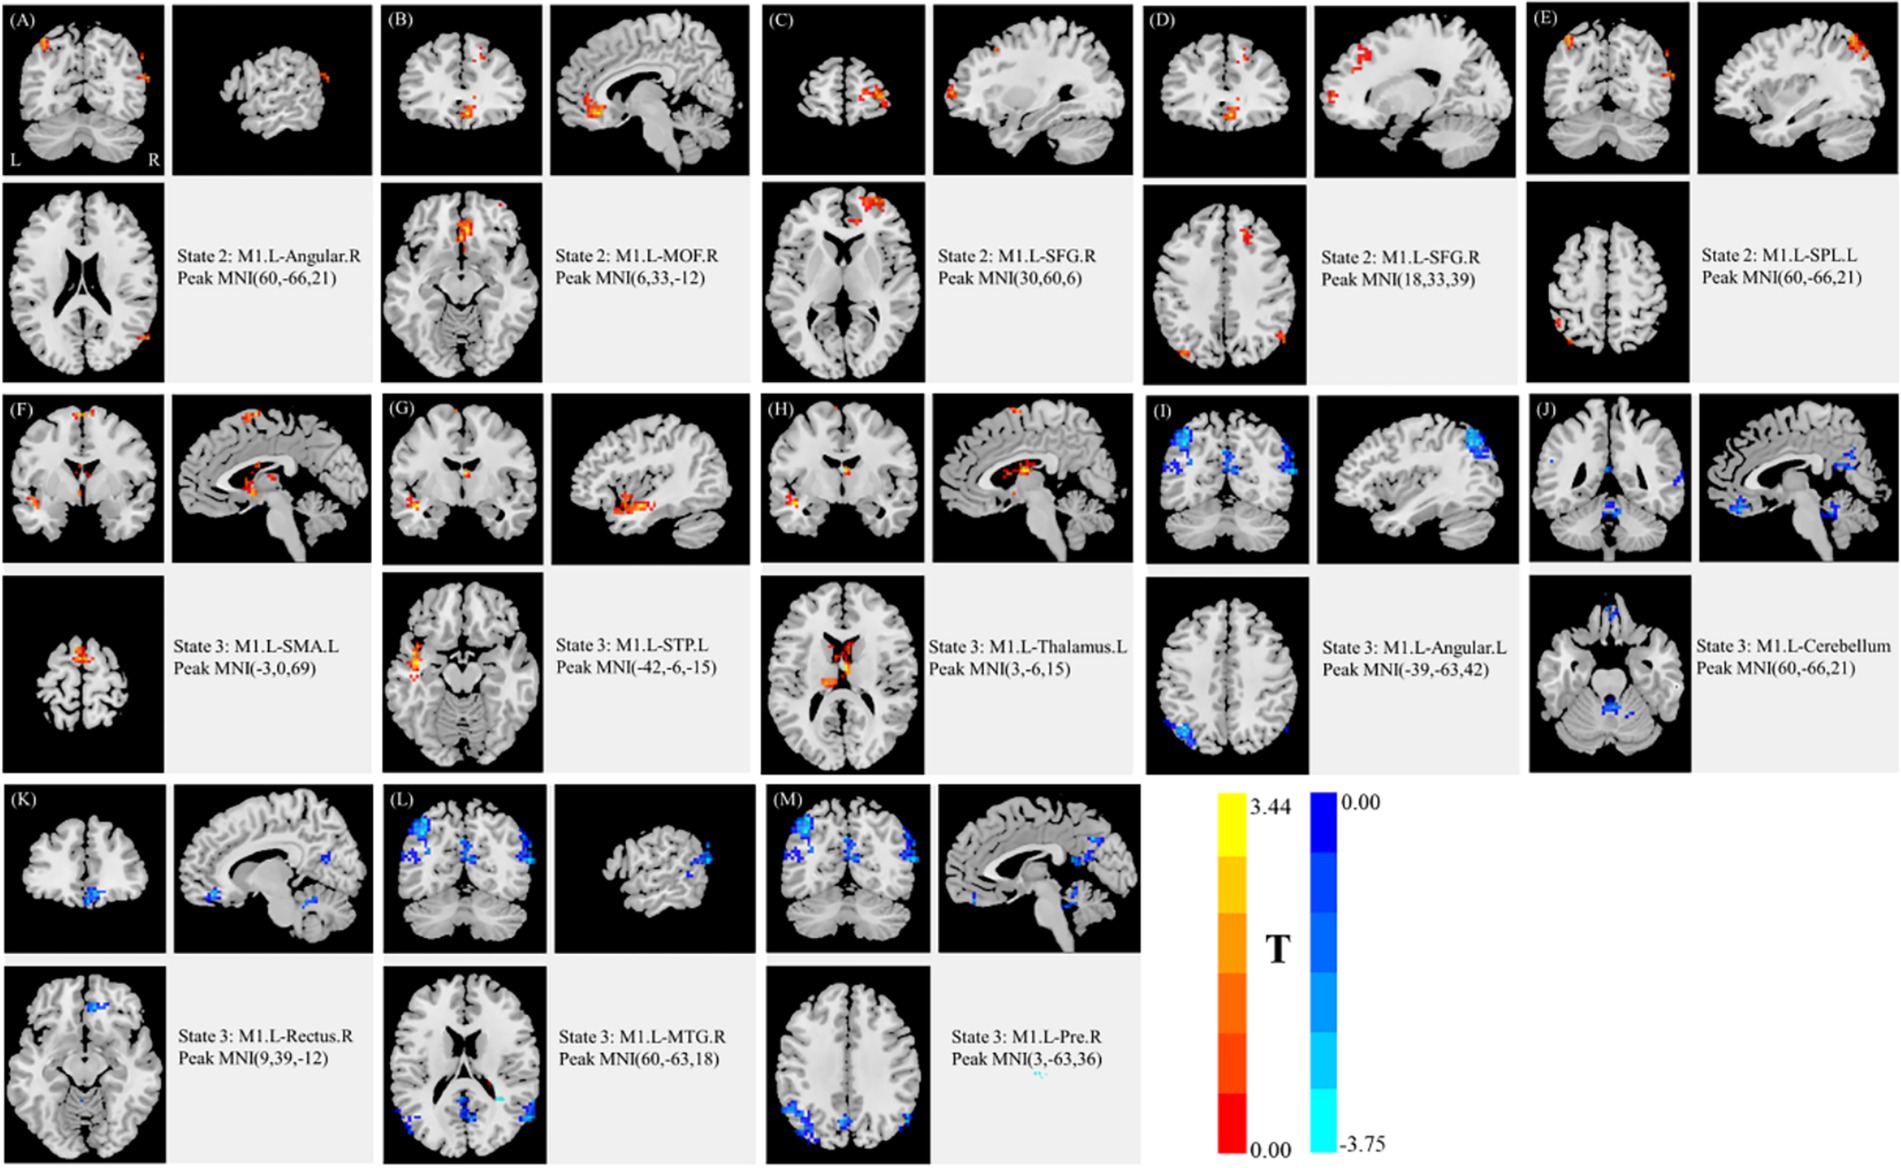

Lesion volumes were manually delineated on T1- and T2-weighted images by two experienced radiologists using MRIcron software1. Lesions were outlined slice by slice for each patient, with T1-weighted images used for primary outlining and T2-weighted images used for validation. To standardize lesion laterality, all images were mirrored so that lesions were represented on the left hemisphere (Figure 1). The resulting lesion masks were used for visualization, lesion volume calculation, and exclusion of intra-lesion voxels during dFC analysis. Notably, lesion volume was not significantly correlated with UL motor function, as measured by UL-FMA scores (Pearson’s r = −0.208, p = 0.087), suggesting that stroke size alone did not account for impairment severity in this cohort.

Figure 1

Overlap map of stroke lesions across all participants. Color intensity indicates the number of patients with overlapping lesions at each voxel. Axial slices are displayed along the z-axis from slice 7 to slice 47 in Montreal Neurological Institute (MNI) space (MNI, Montreal Neurological Institute; R, right; L, left).

Discriminative brain regions contributing to the deep learning framework were identified using two-sample t-tests across dynamic states 2 and 3. Significant regions included the angular gyrus (Angular), MOF, SFG, SPL, SMA, superior temporal pole (STP), thalamus, cerebellum, gyrus rectus, middle temporal gyrus (MTG), and precuneus. Uncorrected t-values indicated group differences in functional connectivity: indices A-E corresponded to state 2 (t = 2.64–3.37), and indices F-M corresponded to state 3 (t = 2.88–3.75) (Table 4 and Figure 4). In Figure 4, red shading denotes regions where functional connectivity was higher in the MSP group compared to the SSP group, while blue shading indicates higher connectivity in SSP relative to MSP.

Figure 4

Discriminative features of selected states. (A–E) correspond to state 2, and (F–M) correspond to state 3, respectively. L, left; R, right; Angular, angular gyrus; MOF, medial orbitofrontal cortex; SFG, dorsolateral superior frontal gyrus; SPL, superior parietal lobule; SMA, supplementary motor area; STP, superior temporal pole; Thalamus, thalamus; cerebellum, cerebellum; Rectus, gyrus rectus; MTG, middle temporal gyrus; Pre, precuneus; MNI, Montreal Neurological Institute. Two-tailed two-sample t-test, p < 0.05 (|T| > 2.0), cluster size ≥ 50, uncorrected. Red indicates regions where functional connectivity was higher in MSP than in SSP; blue indicates the opposite (MSP, mild stroke patients; SSP, severe stroke patients).

In our 10-fold cross-validation, the 3D-CNN achieved a mean test accuracy of 99.80%. Although deep neural networks iteratively optimize classification weights (24–26, 28), ranking the contribution of individual dFC features remains challenging without feature selection. To address this, we analyzed dFC differences between MSP and SSP across states using k-means clustering. Statistical analysis revealed significant connectivity differences between the ipsilesional M1 and 13 other regions (p < 0.05, cluster size ≥ 50, uncorrected). Prior work has implicated the contralesional cerebellum (46), SMA (49), and contralesional parietal cortex (50) in motor recovery or stroke severity. Our findings are largely consistent with these reports, while also revealing increased connectivity in the ipsilesional SMA and SPL, which may reflect specific resting-state configurations rather than averaged connectivity patterns (22). Notably, significant connectivity differences were observed in the contralesional angular gyrus, MOF, SFG, gyrus rectus, MTG, as well as the ipsilesional STP, thalamus, angular gyrus, precuneus, and cerebellum, consistent with widespread functional plasticity following stroke (12, 23, 37). These regions likely contributed substantially to classifier performance, although additional regions may also play roles through subtle, weighted patterns learned by the network.

Consistent with previous findings, reduced connectivity between the ipsilesional M1 and contralesional hemisphere is observed after unilateral motor network damage (12). Conversely, increased connectivity within ipsilesional regions may reflect compensatory plasticity. In state 2, MSP patients exhibited higher connectivity in the contralesional angular gyrus, MOF, SFG, and ipsilesional SPL, suggesting better preservation of interhemispheric integration relative to SSP. State 3 revealed more complex patterns: MSP patients showed higher connectivity in the ipsilesional SMA, STP, and thalamus, but lower connectivity in the ipsilesional angular gyrus, precuneus, and contralesional gyrus rectus, MTG, and cerebellum. These results suggest greater network reorganization and motor adaptation in MSP during this state (4), demonstrating a meaningful relationship between dFC patterns and UL-FMA scores (51).